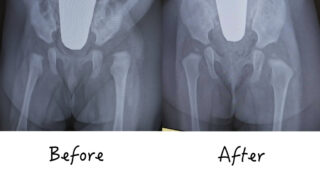

先天性股関節脱臼は、最近は発育性股関節形成不全ともいい、大腿骨頭が骨盤の臼蓋というお皿から外れ、離れてしまった状態のことです。赤ちゃん本人に痛みはないそうですが、治療せずに放置すると将来歩行時に股関節に痛みが出るなどします。早期発見できれば手術せずに治ることがほとんどのようです。五輪マラソンのメダリスト有森裕子さんは先天性股関節脱臼だったそう。心強いですね。

75度で開いた状態を保ち、徐々に錘を軽くしていきます。そうすると大腿骨頭が臼蓋に収まっていきます。期間は1週間程度。第三段階は治療の要で、錘を外すことはならず、当然抱っこはできません。